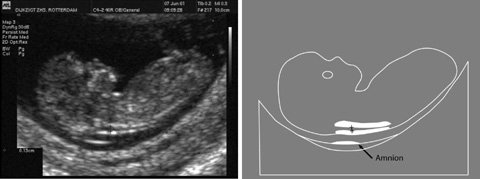

Wat Is Een Nekplooi. Zoals eerder aangehaald is de nekplooi een translucent gebied te zien op echografie die normaal verdwijnt na 14 weken zwangerschap. Toch willen wij het zeker weten. Wat is de nekplooi. Bij een zwangerschapsduur tussen 11 en 14 weken is bij elke foetus een klein schilletje vocht onder de huid in de nek aanwezig.

De specialist in het radboud ziekenhuis zei dat het echt heel normaal is dat de nekplooi vóór 11 weken en 3 dagen nog dikker kan zijn omdat de lymfe zich dan ontwikkelen. Mischien heeft de specialiste een ander reden voor verder onderzoek denk dat je dat best eens kan vragen. In het nekje is dan vaak een beetje vocht aanwezig deze vochtophoping is gewoonlijk niet meer dan 3 mm dik. Zoals eerder aangehaald is de nekplooi een translucent gebied te zien op echografie die normaal verdwijnt na 14 weken zwangerschap. De breedte van dit schilletje wordt gemeten tot op 01 mm nauwkeurig. De nekplooi is een dun vochtlaagje onder de huid in de nek.